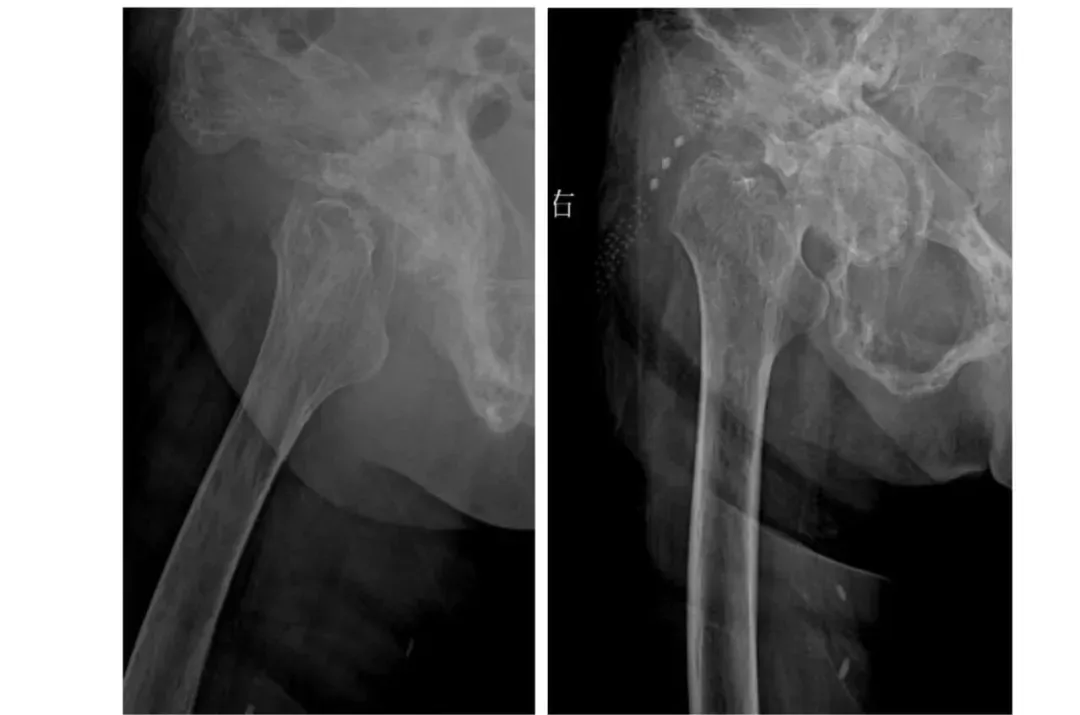

案例三

92歲的患者因“右髖部疼痛不適半月”入院。入院診斷為右側(cè)股骨頸頭下骨折,伴有骨盆畸形、重度老年性骨質(zhì)疏松癥、支氣管擴張癥、冠狀動脈粥樣硬化性心臟病、陳舊性心肌梗死、慢性心力衰竭、心功能Ⅱ-Ⅲ級、主動脈瓣返流(輕度)、低鉀血癥等多系統(tǒng)疾病。入院后,患者接受了全面的輔助檢查,并給予患肢抬高制動、止痛、補液、皮牽引等對癥治療。多學(xué)科團隊(MDT)進行了綜合評估和術(shù)前討論,決定行右側(cè)人工股骨頭置換術(shù)。

術(shù)前

術(shù)后

術(shù)后,在醫(yī)護人員的精心照料下,患者恢復(fù)良好,右髖部疼痛明顯減輕,活動能力逐步恢復(fù)。